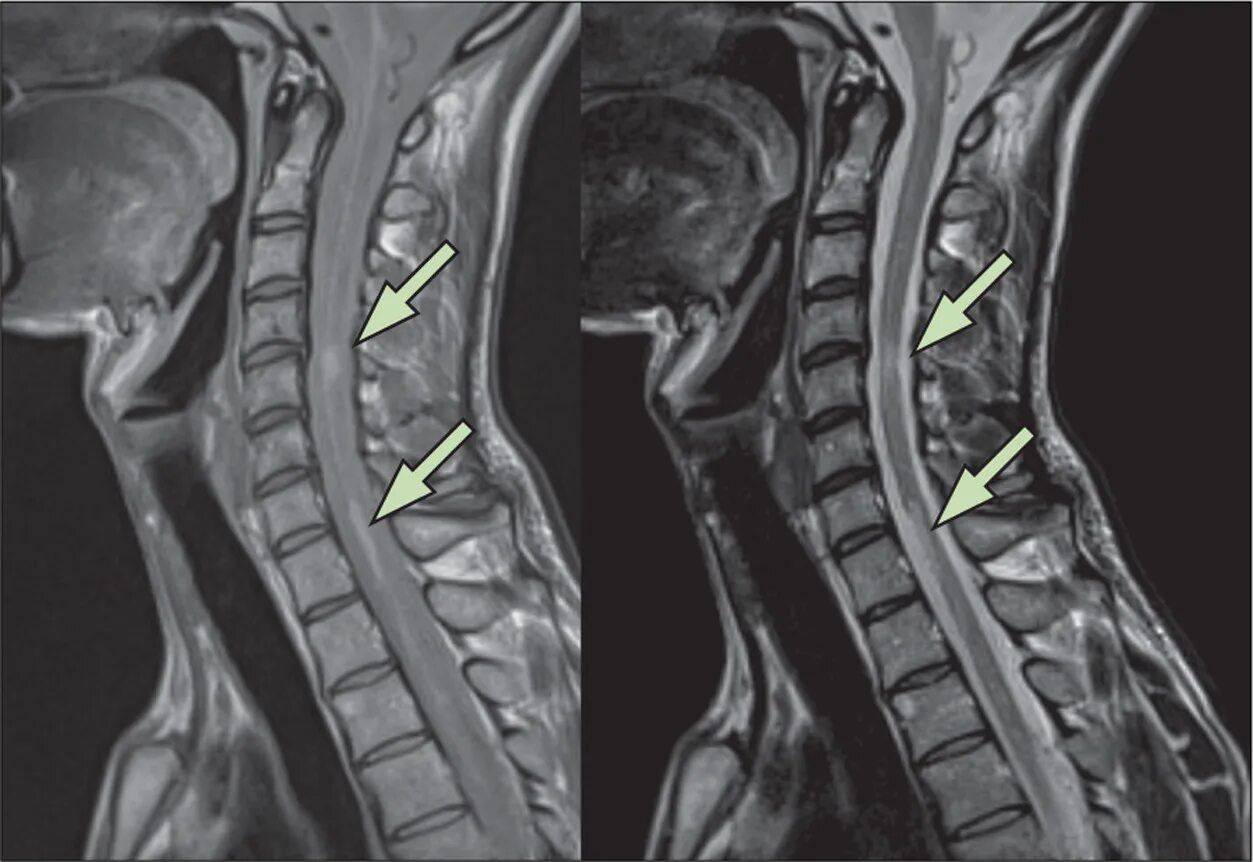

Спайк спинного мозга